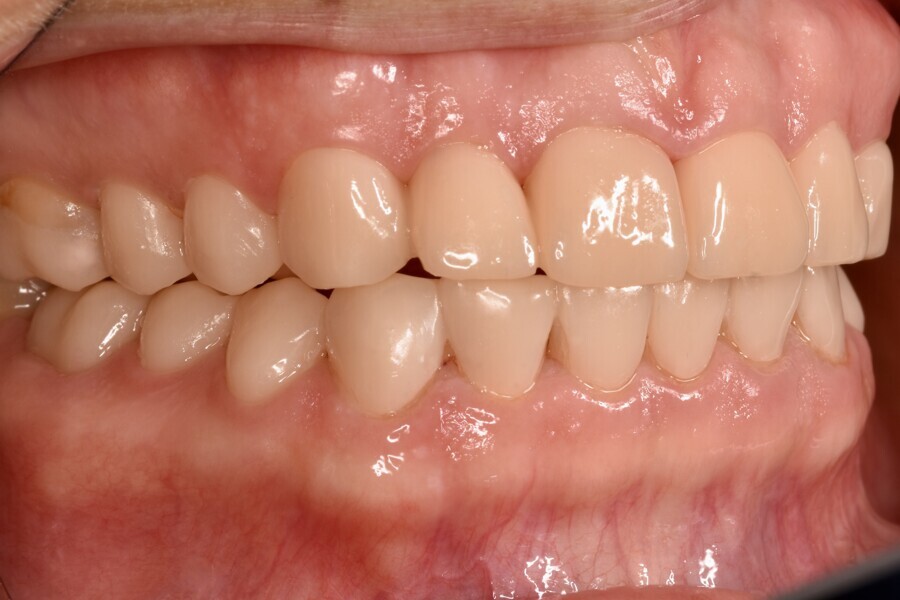

After a dripping time of 10 minutes, unpolymerised resin residue was removed from the printed objects using a brush soaked in isopropanol. The objects were then detached from the build plate, and the supporting structures were removed. Post-polymerisation was performed 15 minutes after the last isopropanol contact, using two cycles of 2,000 flashes each in the Otoflash G171 (NK Optik). After post-processing, the provisional restorations were finished and polished to a high gloss (Figs. 10a-g). Finally, the temporary luting was completed with a dual-polymerising temporary luting composite (Bifix Temp, VOCO; Figs. 11a-e).

After the provisional restorations had been worn for six months, the newly defined occlusal relationship was transferred to final restorations. Adhesively fixed restorations made of monolithic lithium disilicate (IPS e.max Press, Ivoclar) were the first choice (Figs. 12 & 13). Owing to the thin margins in some areas, it was preferable for the restorations to be fabricated using the press technique.